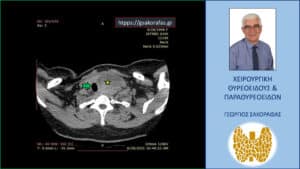

Αξονική τομογραφία – εγκάρσια διατομή. Ο ευμεγέθης όζος (κίτρινος αστερίσκος) απωθεί προς τα δεξιά την τραχεία (πράσινο βέλος).